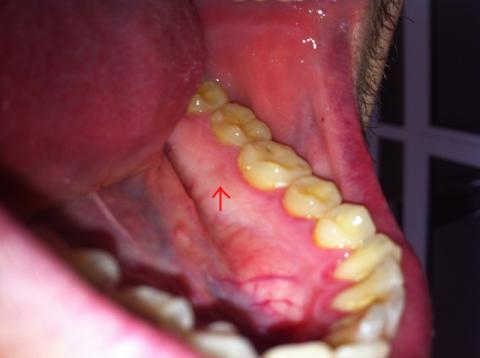

Pred mesiacom sa mi na dasne urobila silno cervena skrvna o priemere cca 0,5cm s viditelnymi okrajmi, po mesiaci doslo ku znacnenemu zlepseniu, polovica z nej zmizla uplne ale zvysok je este stale slabucko viditelny (omnoho slabsie ako to bolo povodne). Poprosil by som teda o radu o co sa moze jednat? Moze to byt sposobene zapalom dasien/Gingivitída (ktory zjavne mam)? Hlavna otazka, nemoze sa jednat o vaznejsie ochorenie ? Zubar mi povedal ze tam nemam nic :/. Prikladam aj foto. Za vsetky odpovede vam vopred dakujem.

Dobrý deň, Váš pán doktor má ale pravdu. Ani fotka nič patologické neukazuje. Takže si osobne myslím, že vaše obavy sú úplne zbytočné.